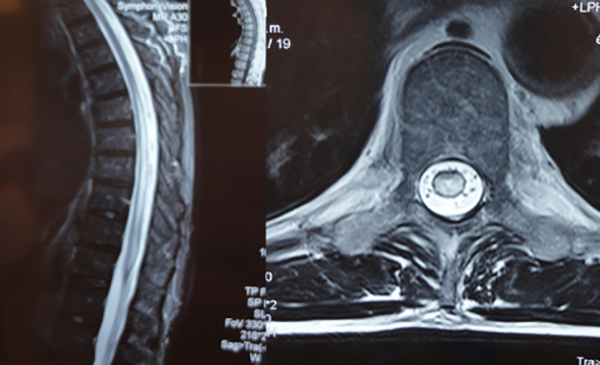

Figura 9: Caso #2. RMN preoperatoria en secuencia T2, a la izquierda se observa en el corte sagital el característico edema centromedular multisegmentario. A la derecha se aprecia, en el corte axial, los múltiples vasos perimedulares y el edema centromedular.